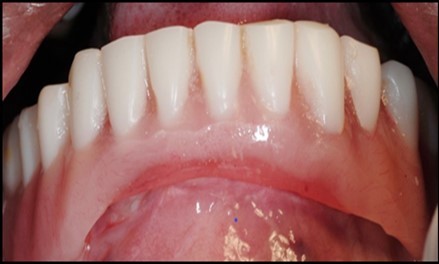

A transferable mark with an indelible pencil is placed on top of each ball abutment and old denture is seated to ideally determine the location for attachment housings. It is followed by preparation of recesses in the intaglio surface of the denture to accommodate the housings (Figure 7B). Lingual vent holes are made for escape of excess acrylic. Placement of nylon processing insert into each of the housings is done with insert seating tool. Figure 8 Seating of the attachment housing onto each ball type abutment is done (Figure 9). Undercuts are blocked out under the housing and soft tissue to prevent acrylic resin from locking the denture onto the abutment. Application of self curing acrylic is done into recessed area and around titanium housings for bonding of the housings to denture. Insertion of denture was done and guiding the patient into proper occlusion with the opposing arch. After the curing of acrylic, denture is removed. Excess acrylic is removed around the housings and lingual vent hole later it is polished (Figure 10). Replace nylon retention insert instead of processing insert into the housings. The insert must seat securely in place and be in level with the housings rim. Overdenture is seated over the ball abutments (Figure 11). Proper instructions have been given to the patient on insertion and removal of prosthesis (Figure 12). The patient was recalled at 1 week, 3 weeks, 3 months, 6 months follow up appointments.

Figure 11.View of denture after being cleaned and polished

Using 2 implants and retentive anchors for the retention of a mandibular complete denture is, in terms of immediate costs, one of the most affordable implant procedures. 8, 9, 14 With ideal placement of the implant, the stability of the prosthesis is excellent and the lingual dimensions of the denture can in some cases be reduced to the level of mylohyoid line, providing more space for the tongue and greater comfort than with conventional complete dentures.8, 9, 10, 15 However, if the labial musculature is tense or the amount of attached gingiva is limited, the implants should not be placed too deep or too labially, which might prevent gingival growth over the abutments. In those cases, ball anchor abutments with elevated shoulders can be used to improve implant anatomy.8, 9, 10 (Figure 12).